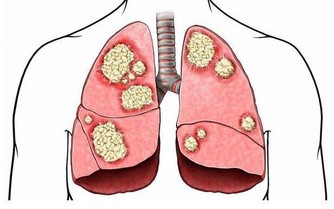

癌前狀態與癌前病變

癌前病變嚴格意義上分兩種,一個叫癌前狀態,一個叫癌前病變,癌前狀態是指患了某些有可能轉化成胃癌的疾病。

癌前病變是指在上述疾病過程中已經發生胃黏膜的不典型增生,這兩類有時統稱為癌前病變。

實際上術語一個是癌前狀態,真正發生了異常增生,從量變到質變才叫癌前病變。

其實所有的腫瘤都是自己身體組織發生了惡變,都是從良性到惡性的過程,所以胃癌也同樣,在它從良性變到惡性的中間過程通常叫癌前病變,這種癌前病變在症狀上、感覺上通常是感覺不到的,需要做檢查,往往要在胃鏡下取病理看看處在一個什麼狀態。

這種病人要格外注意,要做定期的健康體檢,屬於高危人群。

高危人群沒有症狀也需要做體檢,如果有慢性的胃腸疾病更要做定期體檢,尤其當症狀出現了一些變化的時候應該到醫院去接受醫生的檢查。通常來說這種情況一年要做一次胃鏡。